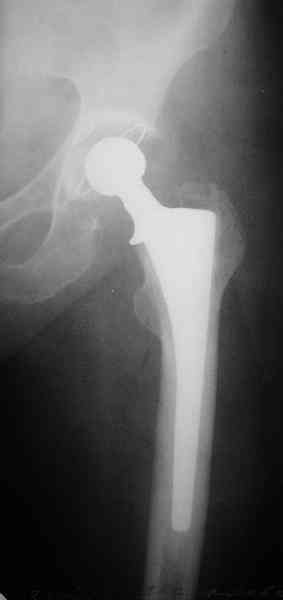

Представленные снимки неудачны ни по качеству, ни по обзорности. Классификационно предположительно Ванкувер В2. Накостный остеосинтез LCP с использованием монокортикальной фиксации в проксимальном отделе.

Представленные снимки неудачны ни по качеству, ни по обзорности.

? На фасных проекциях видно все до коленного сустава - куда ж больше обзорность? Качество IMHO совершенно обычное, приемлемое, весь перелом виден...

Классификационно предположительно Ванкувер В2.

B2 - это перелом около конца ножки с ее нестабильностью. Здесь же перелом б.вертела вдоль всей ножки.

1. Представляющей наибольшую ценность из представленной информации следует считать фасные снимки №3и №4 (если считать по порядку). На снимке №3 не видны ни проксимальный отдел бедра с зоной (линией) перелома - наложение тени, ни дистальная зона (линия) перелома - область не захвачена. Снимок №4 демонстрирует дистальную линию перелома, но не показывает уровень конца ножки эндопротеза. В таких сучаях как способ можно выполнять снимок "с метками" - чтобы при при наложении снимков на негатоскопе иметь целостностное представление о всём сегменте от тазобедренного до коленного суставов.

2. Не совсем так. Перелом В2 (по C. Duncan и B.A.Masri, 1995) - перелом на уровне ножки эндопротеза или непосредственно дистальнее её конца с нестабильностью ножки, но хорошим качеством кости проксимального отдела бедра. Как известно, по статистике - наиболее часто встречающийся тип перипротезного перелома при первичном эндопротезировании. Очевидно - продольное раскалывание проксимального фрагмента в данном случае вызовёт нестабильность ножки.

1. На снимке №3 не видны ни проксимальный отдел бедра с зоной (линией) перелома

Там видно расхождение фрагментов, диастаз чуть медиальнее б. вертела.

Снимок №4 демонстрирует дистальную линию перелома, но не показывает уровень конца ножки эндопротеза.

Кончик ножки виден на самом верху этого снимка.

Вот фрагменты этих снимков с более различимыми областями интереса.